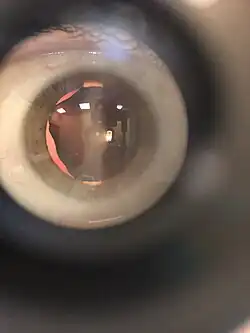

Ectopie du cristallin

Le déplacement du cristallin, ectopie du cristallin, peut être inné ou apparaître à l'âge adulte.

Le cristallin peut se déplacer rapidement mais peut également rester immobile plusieurs années. Si le déplacement est modéré, cela entraîne une myopie d'indice ou un astigmatisme, facilement corrigeables par le port de lunettes correctrices. En revanche, la vue peut être altérée de façon importante si le déplacement dépasse l'axe visuel central de l'œil.

La bascule du cristallin, le plus souvent dans le vitré, peut conduire à des complications oculaires graves, comme le décollement de la rétine.

L'exérèse chirurgicale du cristallin est parfois requise. Une lentille artificielle (implant intraoculaire) peut être mise en place. Mais elle ne permet plus l'accommodation rendant un sujet jeune prématurément presbyte.

Cette pathologie atteint 60 % des individus atteints du syndrome de Marfan.